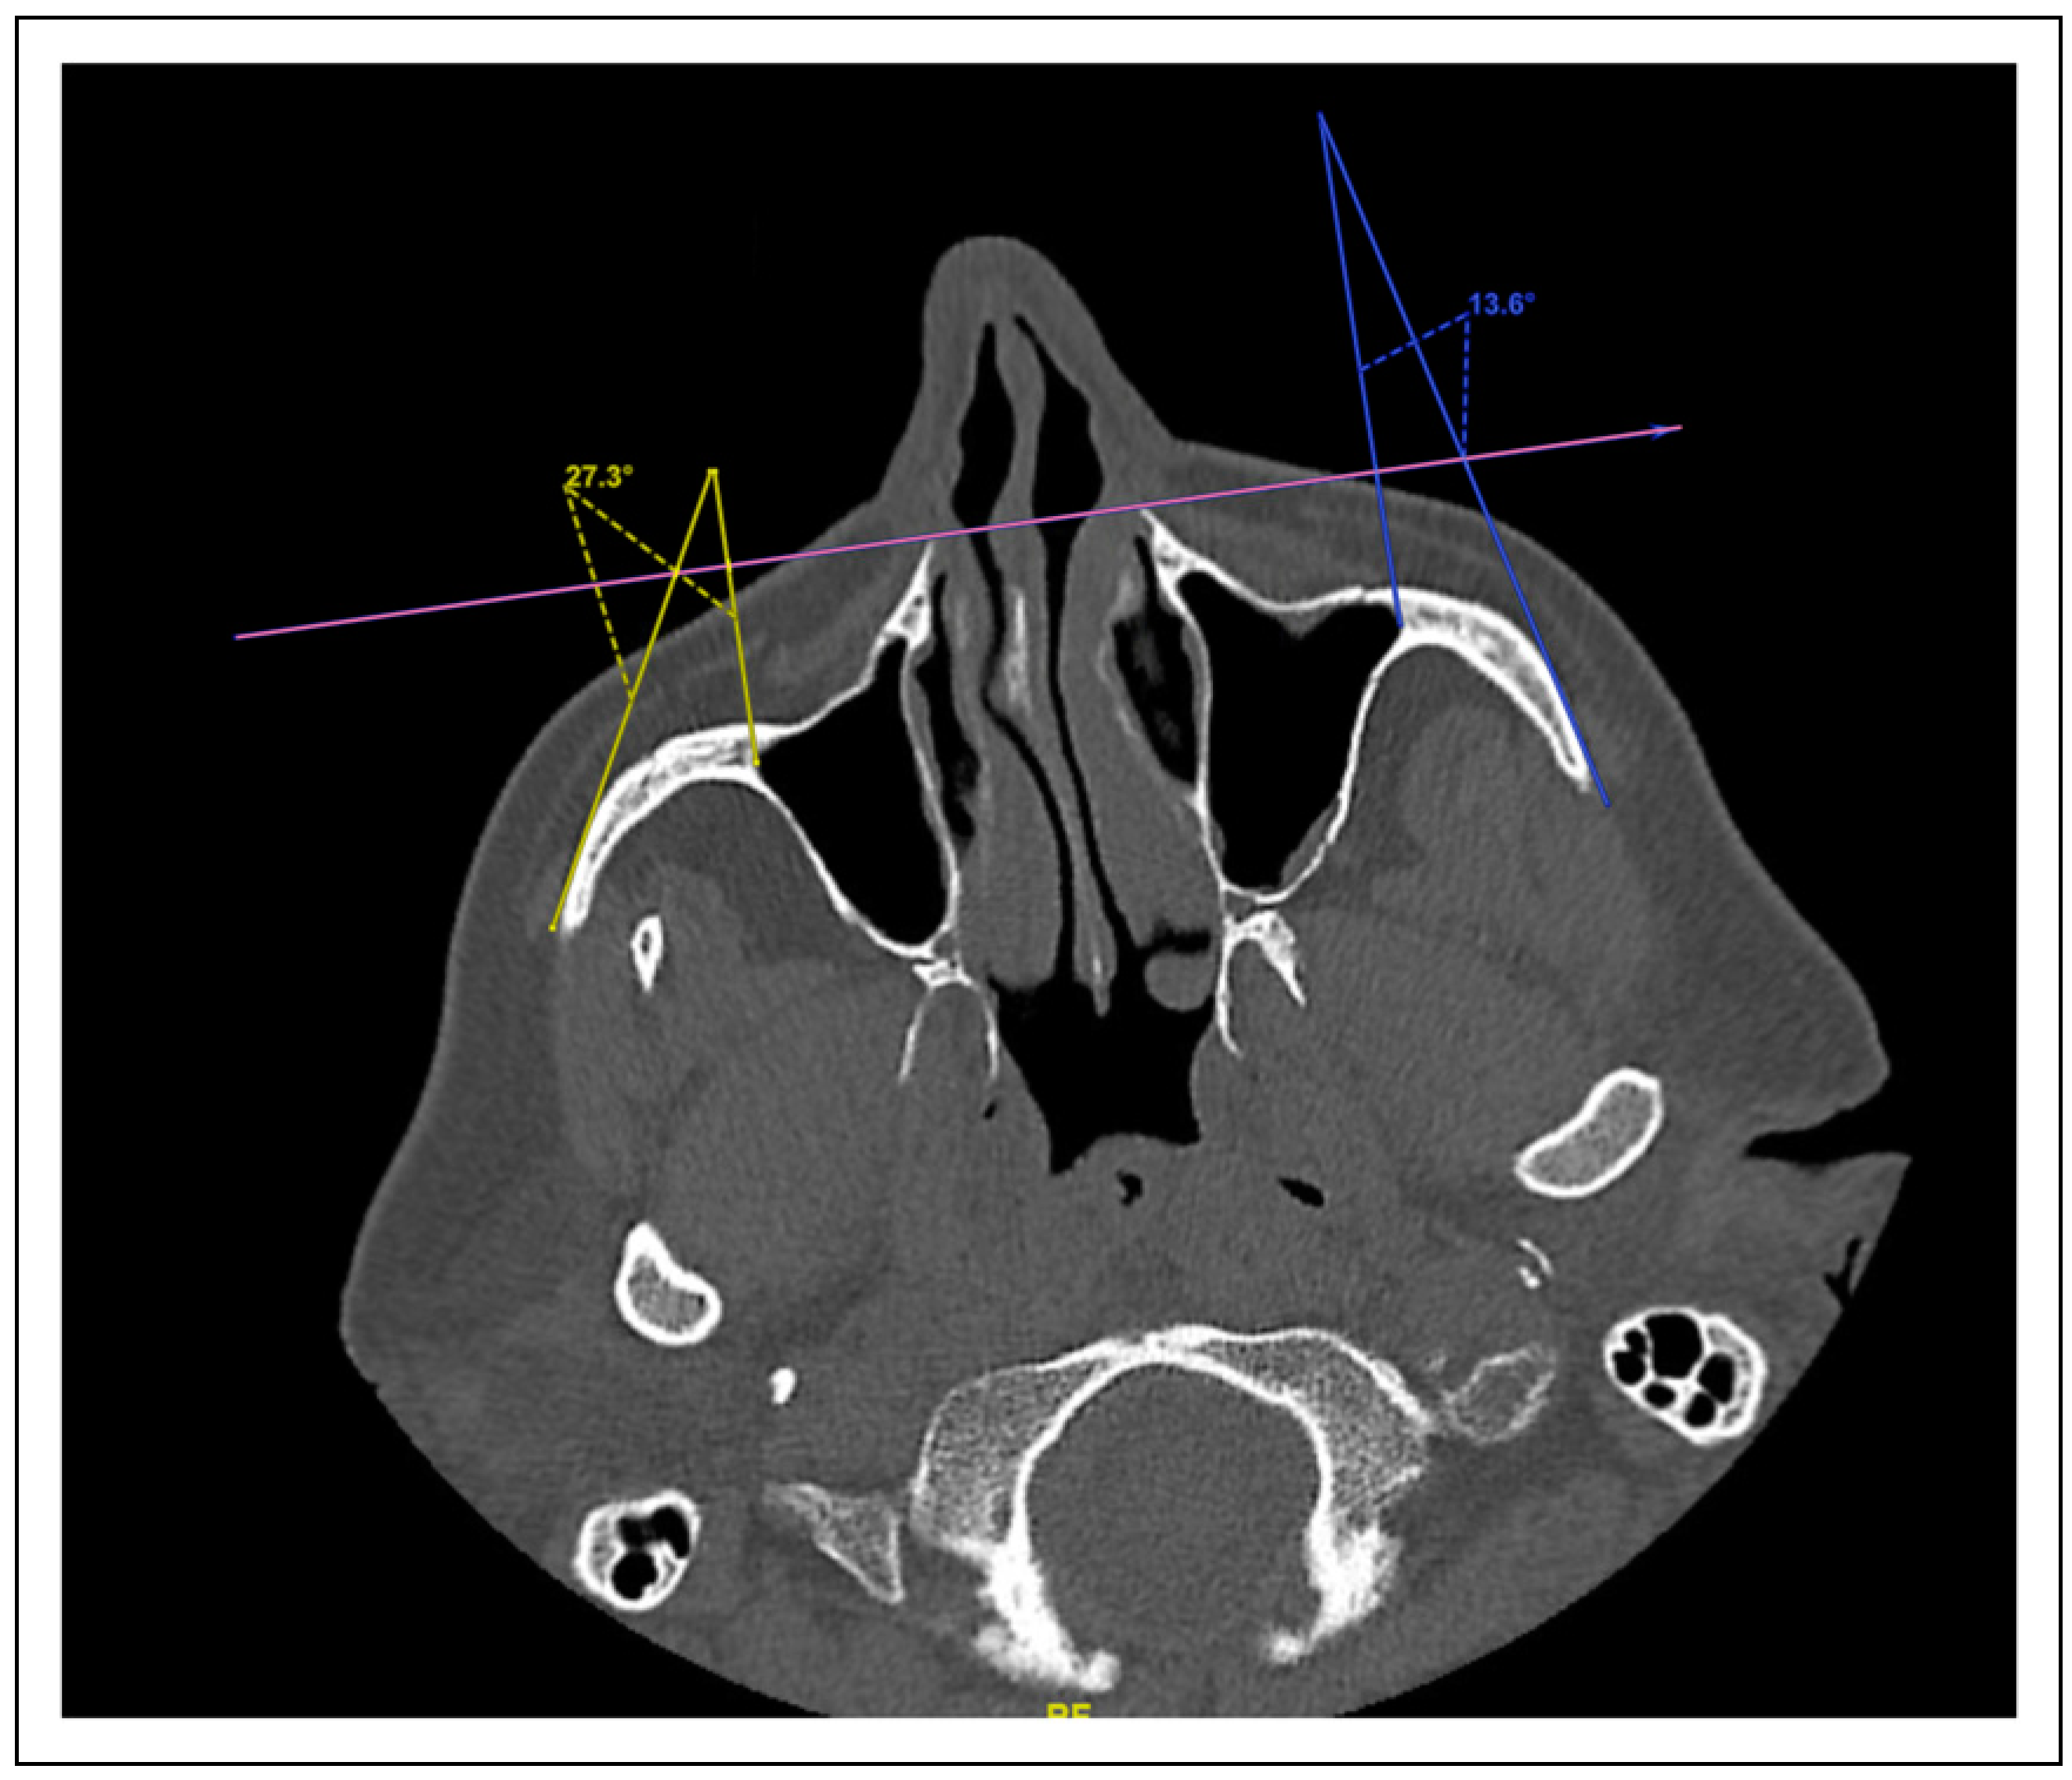

Figure 2. A photo of zygoma body rotation angle. This measurement was standardized using a horizontal reference line that included the anterior-most visible points of the maxillary sinus in the axillary plane. Each angle measurement consisted of 2 lines: the first line perpendicular to the initial reference line with the other endpoint being the most lateral point of the maxillary sinus and the second line an approximation of the straightest edge of the zygoma body. Angle measurements were taken on both the injured and non-injured sides; the degree of rotation was defined as the difference between angle measurements of both sides. External rotation was characterized by acute angles and internal rotation by obtuse angles.

Computed tomography imaging characteristics of the fractures at initial presentation were similarly documented. Data elements measured in this study were (1) medial displacement or impaction of the lateral wall of the maxillary sinus (Figure 1), (2) zygoma angle of rotation (Figure 2), (3) anterior-posterior (AP) displacement of the zygoma (Figure 3), (3) cranial-caudal or vertical displacement of the zygoma (Figure 4), and (4) lateral-medial displacement (LM) of the zygoma (Figure 5). For all vector measurements, the uninjured side served as an internal control.

Zygoma Body Rotation

Degree of zygoma body rotation, as assessed by angle of rotation, was not associated with clinical symptomatology.

When analyzing the various possible displacement vectors for patients with ZMC fractures, we found the critical vectors that significantly predicted clinical symptomatology were lateral maxillary wall impaction (Figure 1), AP displacement (Figure 3), and vertical displacement (Figure 4). LM displacement (Figure 5) did not demonstrate a statistically significant association with any of our collected clinical variables.